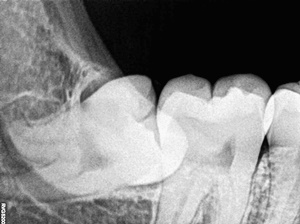

사랑니란?

우리가 사랑니라고 부르는 것은 큰 어금니 중 세 번째 위치에서 제일 마지막에 나오는 치아입니다. 사랑니가 나올 때에는 첫사랑을 하듯이 아프다고 하여 붙여진 이름이라고 하는데요. 다른 이름으로는 ‘지치’라고 합니다. 지치는 사리를 분별할 수 있는 지혜가 생긴다는 뜻입니다.

사랑니는 보통 큰 어금니와 비슷하게 생겼습니다. 사랑니의 형태나 크기는 매우 다양하다고 하는데요. 보통의 어금니 보다 깊이 나기 때문에 빼기 어렵거나 절개를 통해 힘들게 빼야 하는 경우가 많습니다. 원래 사랑니는 음식물을 갈아 내기 위한 용도라고 하는데요. 이것은 치아의 퇴화 현상이라고 생각하시는 분들도 많이 계십니다.